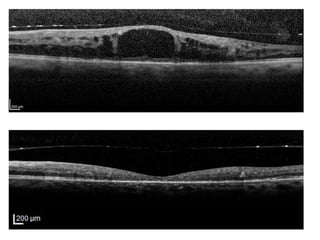

OCT

Tomographie en Cohérence Optique

Œdème maculaire : un véritable gonflement de la rétine